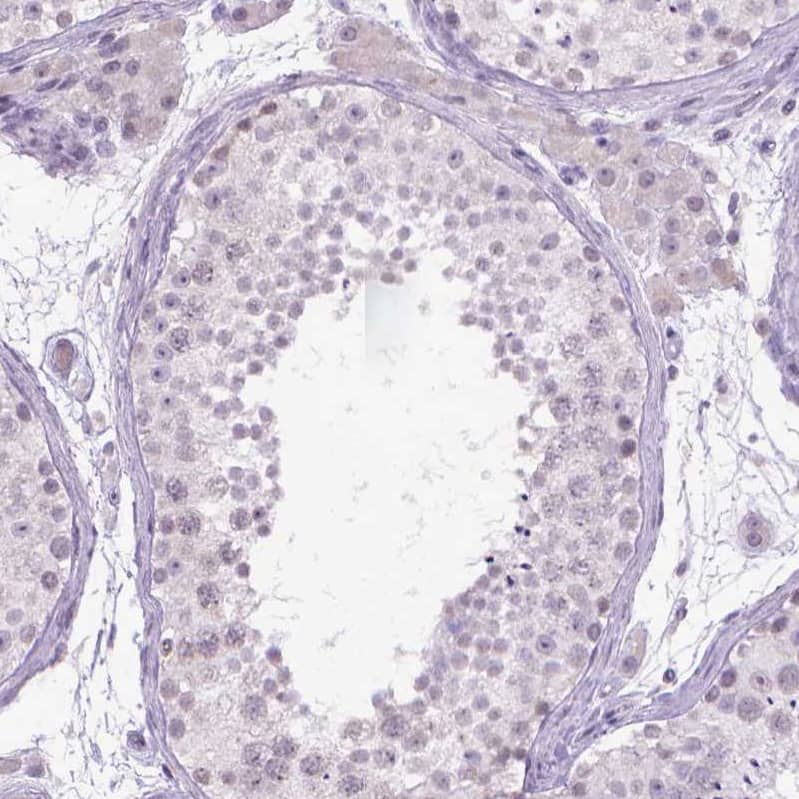

Kynurenine 3-Monooxygenase/KMO Antibody Immunohistochemistry-Paraffin: Kynurenine 3-Monooxygenase/KMO Antibody Antibody [NBP1-86335]

Immunohistochemistry-Paraffin: Kynurenine 3-Monooxygenase/KMO Antibody Antibody [NBP1-86335]

Staining of human endometrium, kidney, liver and testis using NBP1-86335 (A) shows similar protein distribution across tissues to independent antibody NBP2-54915 (B).

Kynurenine 3-Monooxygenase/KMO Antibody - BSA Free Immunohistochemistry-Paraffin: Kynurenine 3-Monooxygenase/KMO Antibody - BSA Free [NBP1-86335]

Immunohistochemistry-Paraffin: Kynurenine 3-Monooxygenase/KMO Antibody - BSA Free [NBP1-86335]

Analysis in human liver and testis tissues Corresponding KMO RNA-seq data are presented for the same tissues.